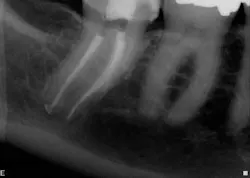

When the anatomy is more complicated than can be predictably treated with WaveOne, but not so irregular as to require all of the files of Vortex Blue, is there another option? It is in these clinical situations that ProTaper Next® (Dentsply Tulsa Dental Specialties) becomes the best file system (Figs. 5 and 6). The rectangular but off-center cross-section creates the illusion that the canal is slightly larger than it is because the alternating contact points of the file prevent the feeling of the file getting locked into the canal space. This added space along the file results in additional room for debris removal, and in spite of this design, there is no appreciable loss of cutting efficiency. When using ProTaper Next files to create the final root canal shape, two or three instruments will be used.

Fig. 6: After locating the canals and following the glide path to the root ends with hand files, two ProTaper Next files were used in each root canal to create the final shape.